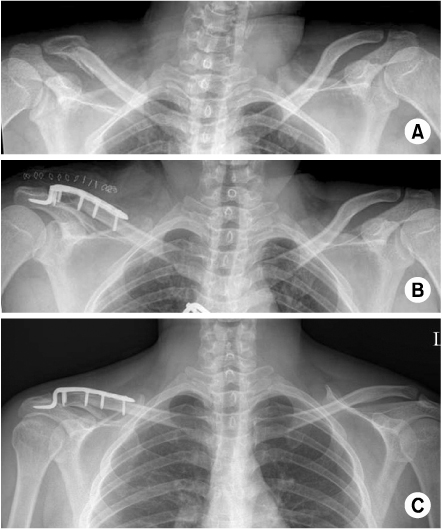

Fig. 3

(A) Preoperative radiograph of the left shoulder of a 49 year old male shows distal clavicle fracture.

(B) This is postoperative radiograph with Hook plate fixation.

(C) At 4 months follow-up, postoperative radiograph shows osteolysis of acromion by the hook of plate.

Fig. 3 (A) Preoperative radiograph of the left shoulder of a 49 year old male shows distal clavicle fracture. (B) This is postoperative radiograph with Hook plate fixation. (C) At 4 months follow-up, postoperative radiograph shows osteolysis of acromion by the hook of plate.